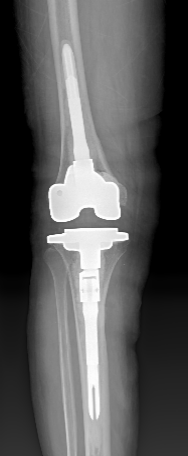

关节外科/运动医学科赵良军副院长、覃刚主任手术团队联合手术室、检验科及临床药学部等MDT团队为患者制定了周密的治疗方案,术前相关检查无明显手术禁忌症,在全麻下顺利完成右侧人工全膝关节表面置换术后感染清创、假体取出、新的假体按装等一期翻修手术。该手术在我院的成功开展,为髋膝关节置换术后感染患者提供了一套新的手术治疗方案。

图5 术后

图6 术后